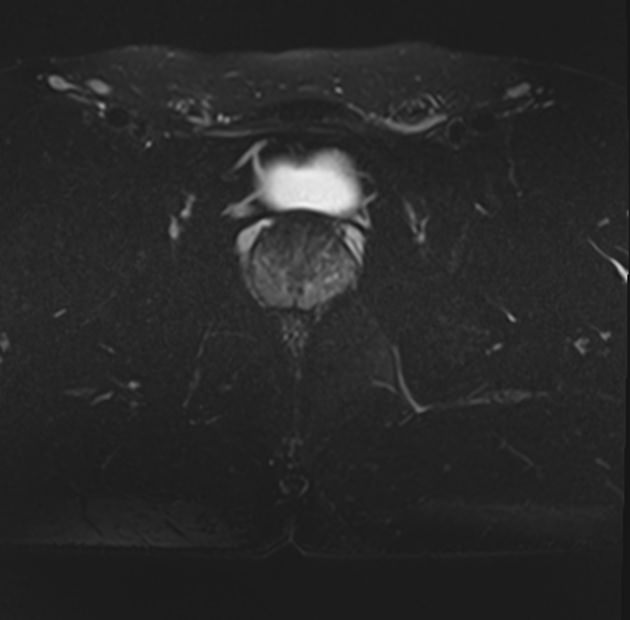

Выполнение МРТ малого таза в стандартном режиме возможно без использования контраста. Однако при подозрении на патологические изменения со стороны органов мужской половой сферы, мочевыделительной системы, прямой кишки или окружающих мягких тканей, обязательным является введение контрастного препарата, имеющего в своем составе гадолиний (редкоземельный металл). Контрастное вещество имеет способность накапливаться в патологически измененных тканях, в частности, в опухолевых очагах. Это используется для диагностики онкологических заболеваний на ранних стадиях, что имеет решающее значение для жизни и здоровья пациента.

структуру предстательной железы, а также выявить происходящее в ней патологические процессы. К примеру, для таких заболеваний, как простатит, аденома простаты (доброкачественная гиперплазия) и рак простаты очень важна ранняя диагностика, что и позволяет МРТ. Для обследования простаты метод МРТ является уникальным по своей информативности.

- Доброкачественные и злокачественные опухоли мочевого пузыря, простаты, семенных пузырьков, прямой кишки, метастазы в тазовой клетчатке и органах малого таза;